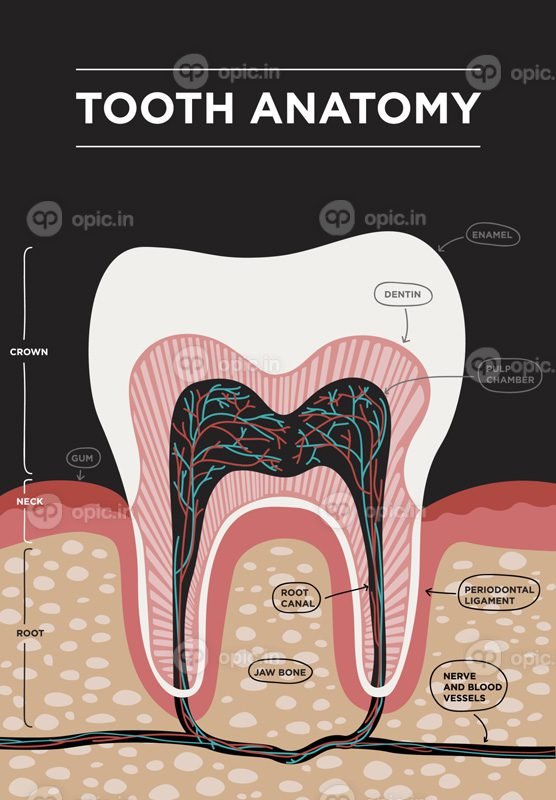

عصب کشی